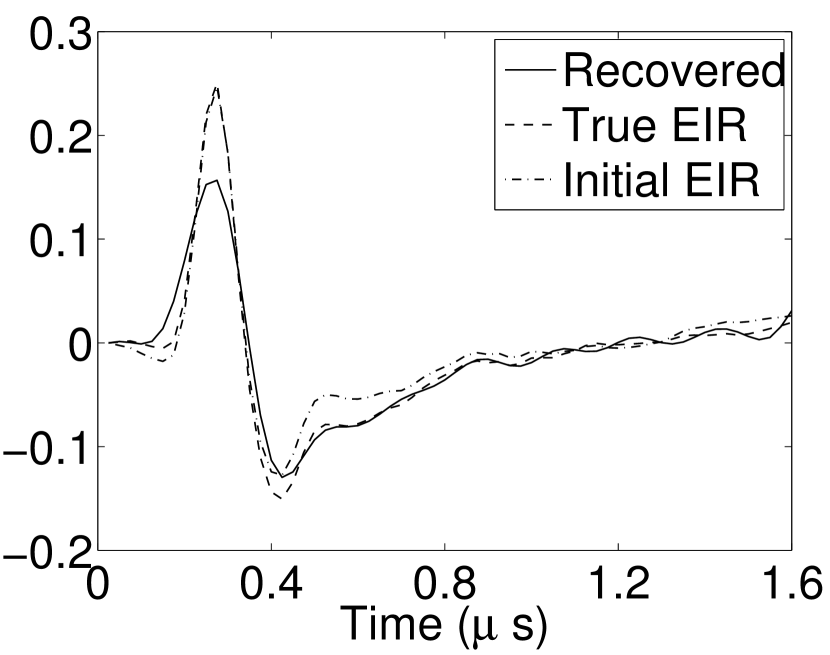

Each element in a real-world transducer array possesses its own EIR. In practice, the differences between the EIRs are sometimes neglected and an EIR corresponding to a single element may be used to represent all elements in the array. In some of the studies below, the EIR employed to initialize the VP algorithm (EIR-2 in Figure 1(b)) and the EIR employed to produce the simulated measurements (EIR-1 in Figure 1(b)) were experimentally measured from two different transducer elements in a circular transducer array (see Sec. VI-B). EIR-1 was measured by temporally integrating the PA signal produced by a point source positioned at the focus of the transducer. EIR-2 was measured by use of the method reported in [RNR2011]. In order to investigate the sensitivity of the VP algorithm to the initialization of the EIR, we employed different EIRs obtained by degrading EIR-1 as described later. When solving the sub-problem in Line-2 of Algorithm 1, was initialized as the zero vector. Algorithm 1 was terminated after 500 iterations, since it was observed that the changes in the reconstructed images with more iterations were negligible. When implemented by use of a single core of an Intel Xeon E5-2640 CPU, each iteration required approximately 7s to complete.

V-A4 Effect of initial estimate of EIR

As shown in Figure 6, when the error in the EIR was small (e.g., as with the EIR in Figure 6(a)), images were reconstructed with high accuracy using the VP algorithm. When the perturbations in the EIR were stronger (e.g, as in Figure 6(c)), artifacts and distortions in the reconstructed images were still significantly reduced by use of the VP algorithm; however, larger values of the regularization parameters had to be applied. When as in the initial EIR in Figure 6(e), no improvement was observed in the image reconstructed by use of the VP algorithm.

Figure 7(a) reveals that use of the inaccurate EIR in the conventional iterative method created strong artifacts and distortions. Figures 7(b) confirms that the artifacts and distortions were significantly mitigated when the VP method was employed. Image profiles for both cases are shown in Figures 7(c). The overall accuracy of the recovered EIR, shown in Figure 7(d) and 7(e), was improved, but it contained spurious oscillations.